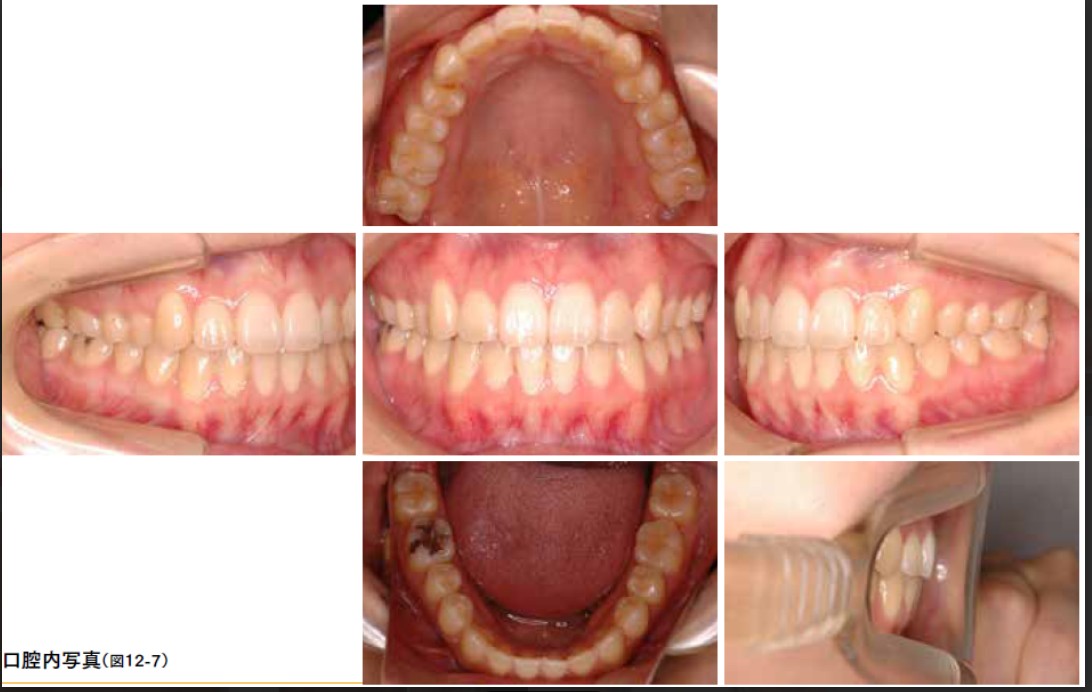

最後に、2年間の矯正治療を終え、その後の保定期間を経て、現在治療終了から8年が経過した症例をご紹介します。保定装置を適切に使用し、指示通りに管理を続けることで、治療後も長期にわたり良好な歯並びを維持することが可能です。

●矯正治療終了:保定期間時

医療法人ヤマジ歯科・矯正歯科クリニック:矯正治療終了保定期間時

●保定期間終了時